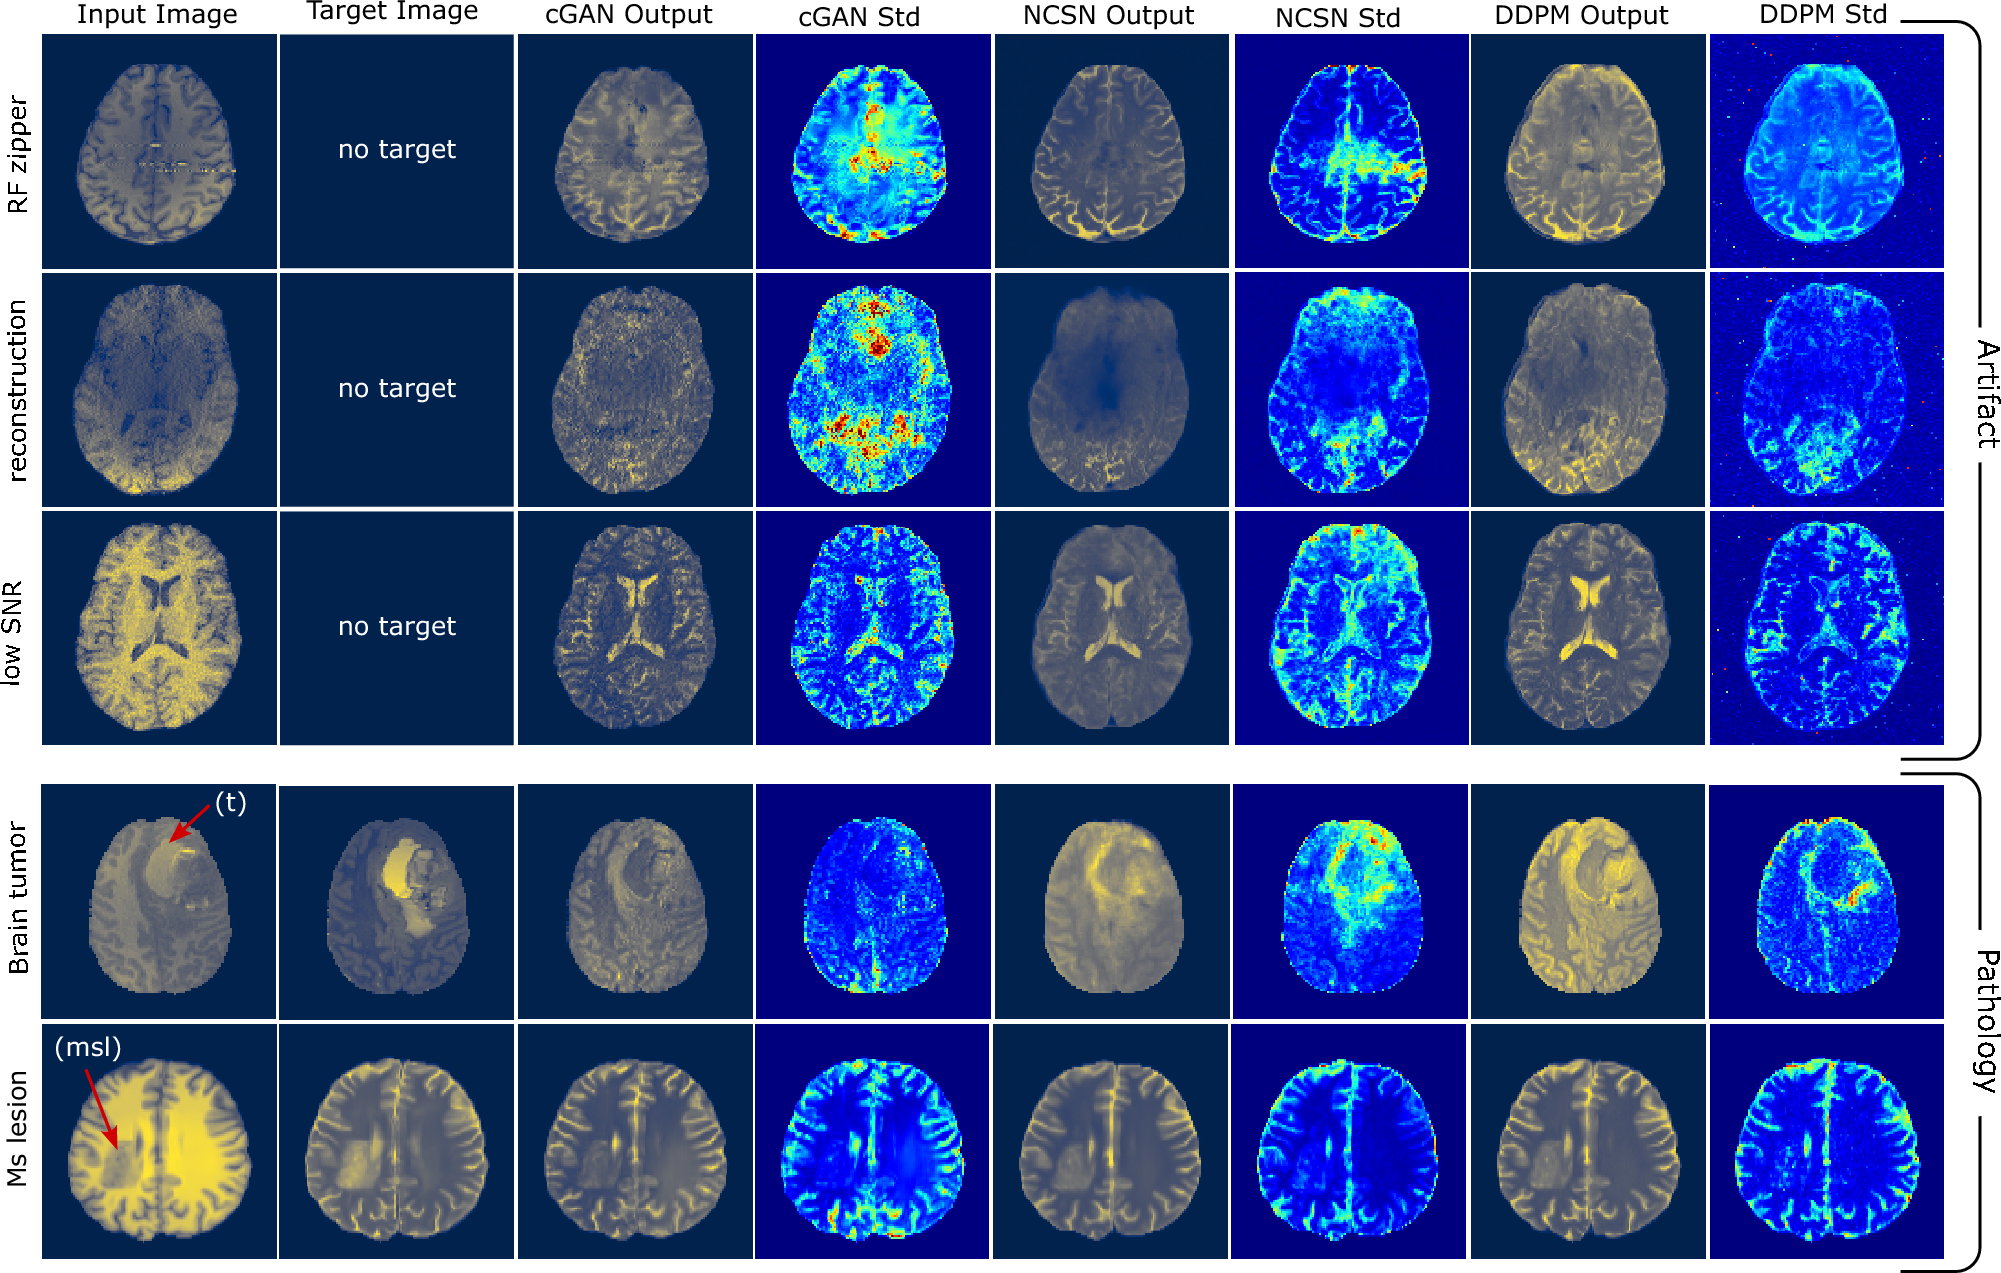

Response of models to out-of-distribution (OOD) input images. Column 1: input image; column 2: target image (when available); column 3-4: output and standard deviation images for the cGAN model; columns 5-6: transformed image and standard deviation for NCSN; columns 7-8: transformed image and standard deviation for DDPM. Rows 1, 2, and 3: images with RF zipper, reconstruction artifact, and low SNR; rows 4-5: images with brain tumor and white matter MS lesion pathologies.